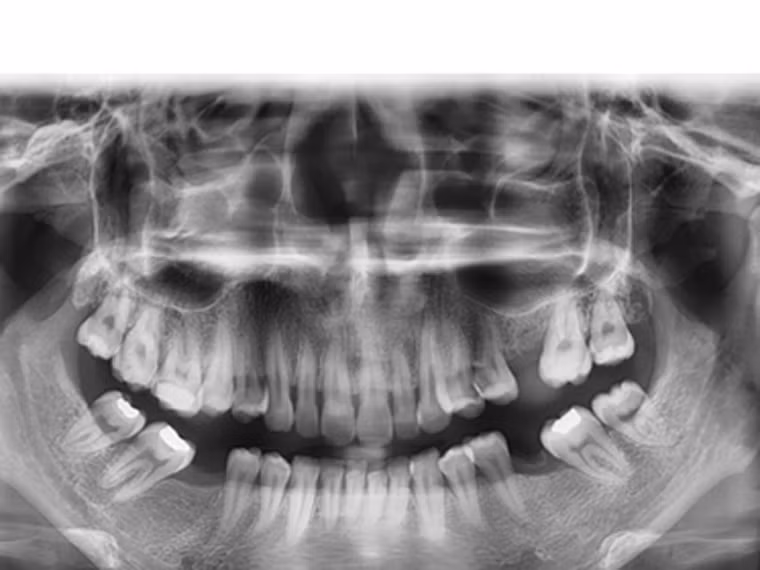

Chụp X- quang là phương pháp cho phép tạo ra các hình ảnh cấu trúc bên trong cơ thể khi sử dụng lượng nhỏ chất phóng xạ. Nếu người bệnh xuất hiện khối u bất thường, hình ảnh X – quang sẽ cho phép xác định vị trí, kích thước khối u. Một trong những lợi thế nữa của chụp X – quang là nó cho phép bạn mở rộng phạm vi kiểm tra ra các vùng như ngực, phổi, tuyến giáp… Rất nhiều trường hợp tình cờ phát hiện khối u khi chụp X – quang.